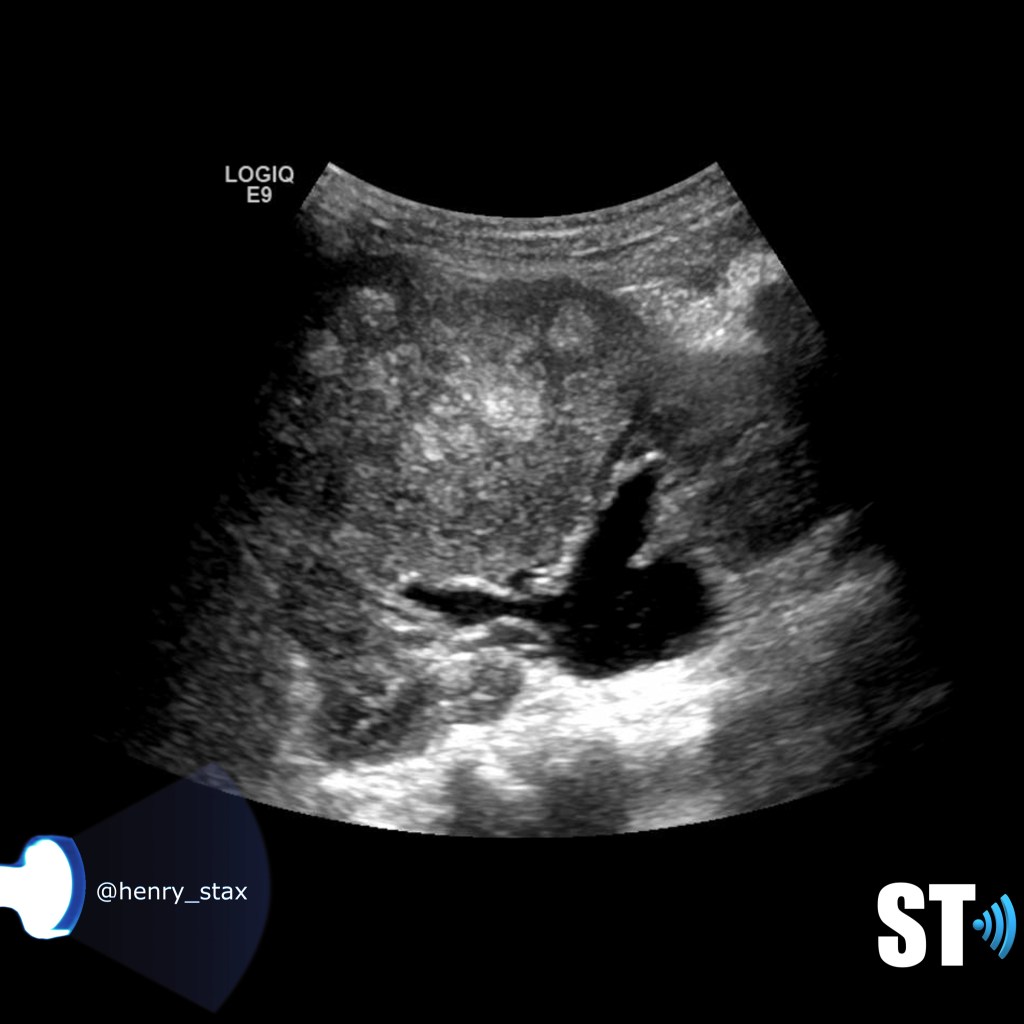

ADPKD

In Autosomal Dominant Polycystic Kidney Disease (ADPKD) the kidneys are normal at birth with cysts developing overtime. By age 30 years, approximately 68% of patients will have visible cysts by ultrasound. Eventually, virtually all patients develop cysts. The disease is transmitted in an autosomal dominant pattern, meaning you only one abnormal gene from one parent.

One abnormal gene from one parent

- Adult

- 4-10% of all cases of ESRF

- Kidneys appear normal early on

- Liver, pancreas and spleen cysts